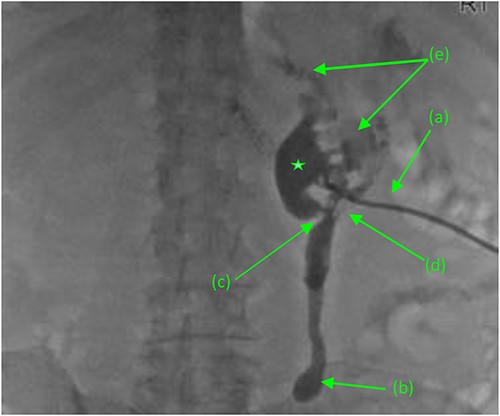

Repeat abdominal CT revealed a fistulous connection between the 3rd portion of the duodenum and the right proximal ureter with oral contrast pooling inferiorly in the mid-distal right ureter (Fig. 1). Nephrostogram confirmed a frank fistulous connection between the proximal ureter and duodenum. Additionally, a second fistula originating from the collecting system superiorly was suspected due to contrast extravasation tracking directly to the 2nd portion of the duodenum (Fig. 2).

Antegrade pyelogram (prone position) revealing (a) right percutaneous nephrostomy tube (PCN), following the failed ureteral stent placement due to a distal ureteral stricture with subsequent (b) right sided hydroureter and abrupt cutoff. (*) Right sided hydronephrosis, secondary to (c) a second, more proximal ureteral stricture with a (d) frank fistulous connection tracking between the proximal ureter and duodenum. (e) Suspected retrograde leakage of contrast media from the right renal pelvis into the duodenum.